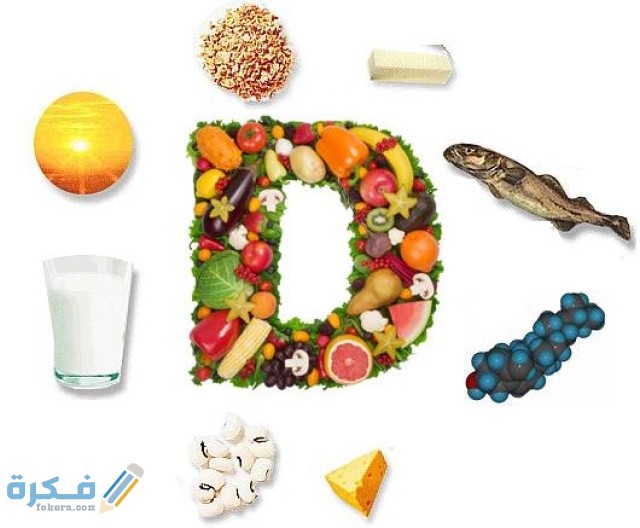

أكمل القراءة »شي يرفع فيتامين د بسرعة من خلال موقع فكرة سوف نستعرض معكم هذا الموضوع شديد الأهمية حيث أن جسم الانسان…